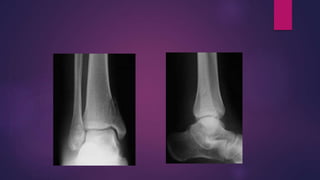

SUPINATION EXTERNAL ROTATION